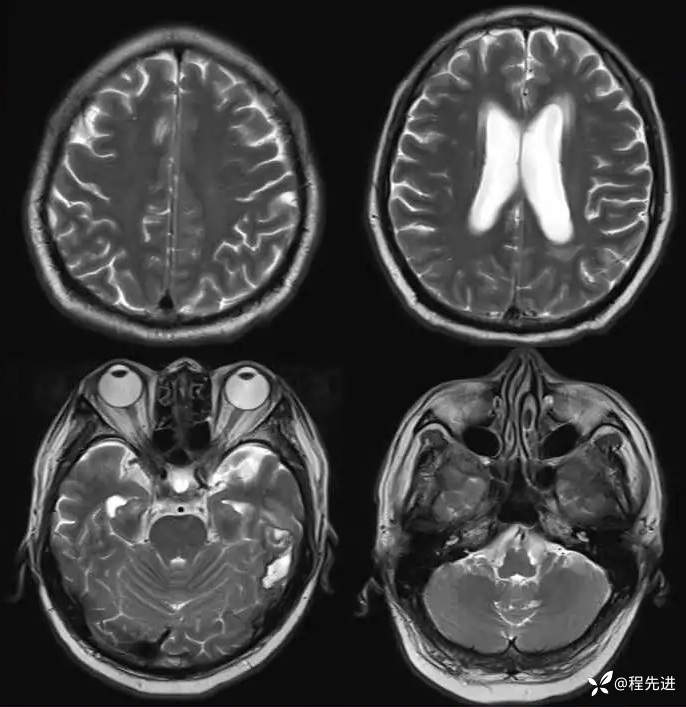

MR平扫+增强: